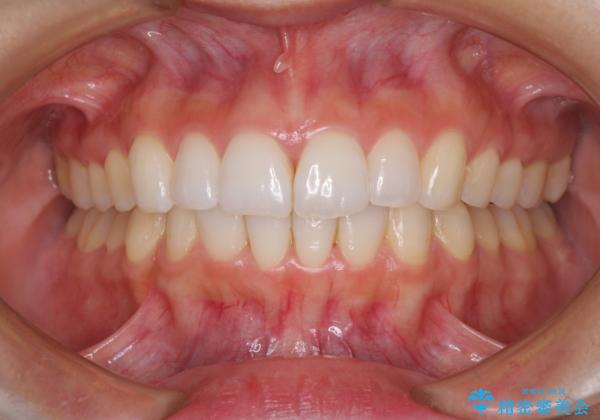

結婚式までに前歯を整えたいとのことでしたが、インビザラインでは先に奥歯を移動させてから前歯を動かすため、間に合わない可能性がありました。しかし、結婚式までに期間があったことと、マウスピースをしっかりと装着してくださったことで、十分な歯列に整えることができました。

楽しく通院していただき、辛いと思っていた治療もあっという間であったそうで、患者様には大変満足していただきました。